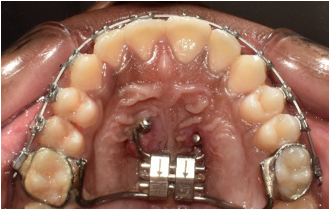

After the leveling and alignment period, treatment had to be halted, due to Covid-19 and the patient being unable to come for appointments due to travel issues. After 18 months, treatment resumed with the placement of hybrid hyrax, for disarticulating the circummaxillary sutures to facilitate maxillary protraction. The Hyrax was placed at the mid palatine rugae, with its buccal arms extending anteriorly to the first premolar region and the posterior arms were welded to bands on the first permanent molars (16 and 26). The anterior arms of the hyrax consisted of two rings at the anterior palatal region for the insertion of mini-implants. Under local anaesthesia, two mini-implants (SK Surgicals) (2 mm diameter, 10 mm length) were inserted, at the level of the second and third palatal rugae, adjacent to the midline suture.([Figure 2])